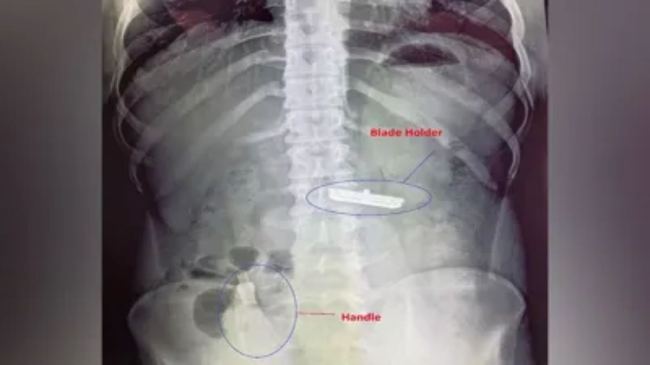

Shaving Razor Removed From Delhi Man Stomach: दिल्ली में एक हैरान कर देने वाली घटना सामने आई है। दरअसल, यहां के सर गंगा राम अस्पताल में 20 वर्षीय युवक पहुंचा। युवक ने पेट में शेविंग रेजर होने की बात बताई। पहले तो डॉक्टरों को इस पर भरोसा नहीं हुआ। लेकिन उसके पेट का एक्स रे करने के बाद सब चौंक गए।

युवक के पेट में ब्लेड और रेजर का हैंडल दो हिस्से में साफ दिखाई पड़े। हैंडल तो आंतों में फंसा था जबकि ब्लेड होल्डर उसके पेट में घुसा हुआ था। तुरंत इस मामले की सूचना सीरियर डॉक्टरों को दी गई और युवक के ऑपरेशन के लिए डॉक्टरों की टीम बनाई गई। डॉक्टरों ने कड़ी मशक्क्त के बाद युवक के पेट से ब्लेड होल्डर और उसका हैंडल बाहर निकाला। सर्जरी के बाद अब युवक पूरी तरह स्वस्थ है।

डॉक्टरों के अनुसार ये बेहद पेचीदा केस था, अगर थोड़ी और देरी होती तो आंतों पर ज्यादा नुकसान हो सकता था। युवक की मनोवैज्ञानिकों से काउंसिलिंग करवाई जा रही है। अब वह पूरी तरह ठीक है और उसे हल्की डाइट पर रखा गया है। डॉक्टरों के अनुसार युवक की लैपरोटॉमी की गई थी, जिससे ब्लेड कहां है? इसका पता चला और फिर उसे निकाला जा सका है।